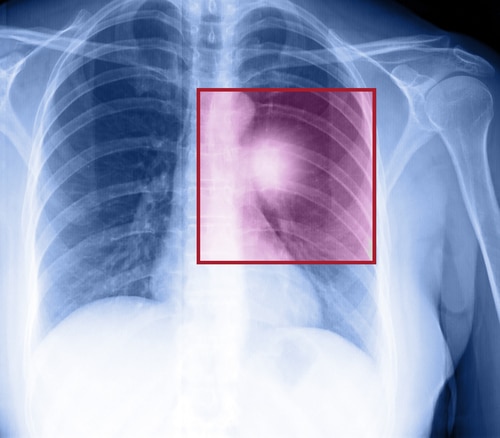

We put our trust in our doctors to help us get better. Sometimes doctors act outside of the standard of care which causes harm to you. In such instances, you may be entitled to compensation for any damages you faced because of this breach of duty. One of the biggest reasons people have medical malpractice cases is failure to diagnose.

It is important to note that not every instance of failure to diagnose will warrant a claim. However, if you are caused serious harm, or a loved one’s death was due to a failure to receive proper and timely diagnoses, that will warrant a claim.

- Your doctor failed to send you to get testing.

- Your doctor did not interpret your lab results correctly.